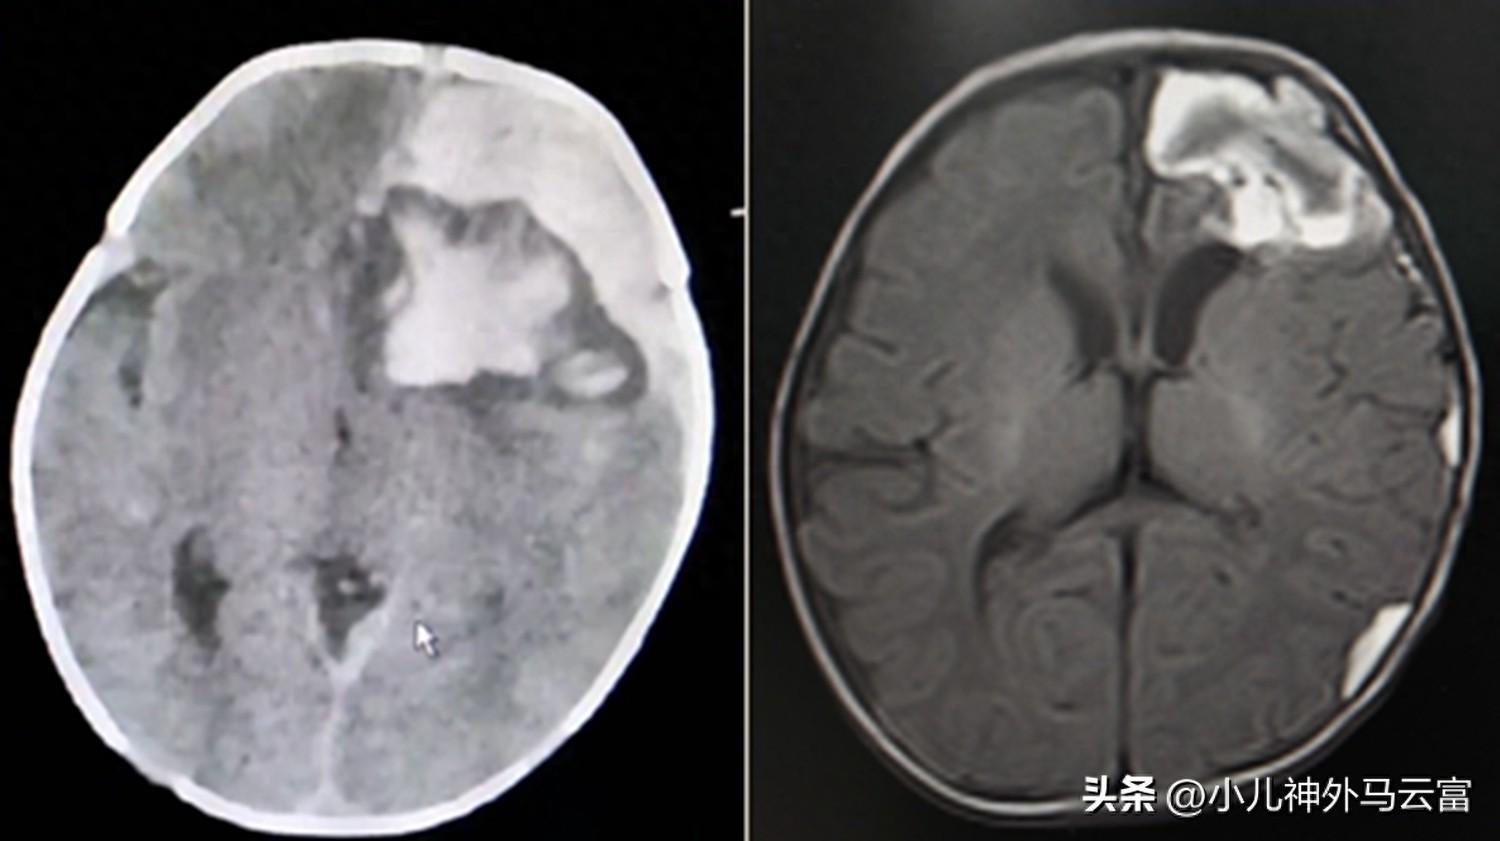

管牀醫生熊瑩瑩及時完善了頭部CT檢查,顯示左側額顳葉大量出血,腦室移位,腦疝,並立即聯繫了小兒神經外科會診。

湖北省婦幼保健院小兒神經外科馬雲富主任、夏星主治大夫在瞭解患兒的病因和影像學檢查後表示:“左側額顳葉大量出血,腦室移位,血腫量大,壓迫腦幹,有手術指徵,需要及時清除血腫,解除血腫對大腦的壓迫。若選擇保守治療,血腫壓迫腦幹及大腦,會引起顱內壓繼續增高,形成腦疝危及生命”,建議手術治療。